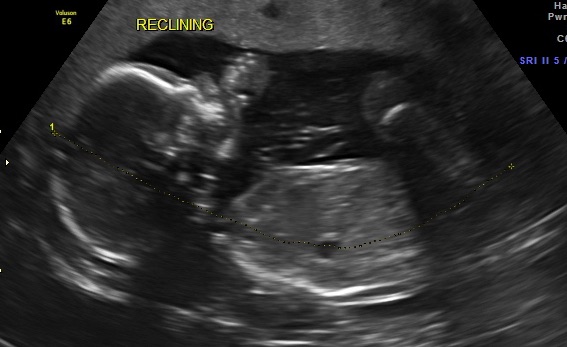

Bawling, unable to control myself any longer, we went back and got to see our little boy. I'm assuming my favourite nurse did some explaining because the technician was so nice and showed us everything, explaining it all, gently with compassion.

Baby boy is looking great, everything is as it should be. The relief I feel is honestly dizzying.

Though we aren't announcing his name to everyone, I love saying it, and would like to introduce Finn's little brother:

Oliver Heath M ❤️

I'm so in love. I can't stop staring at him.